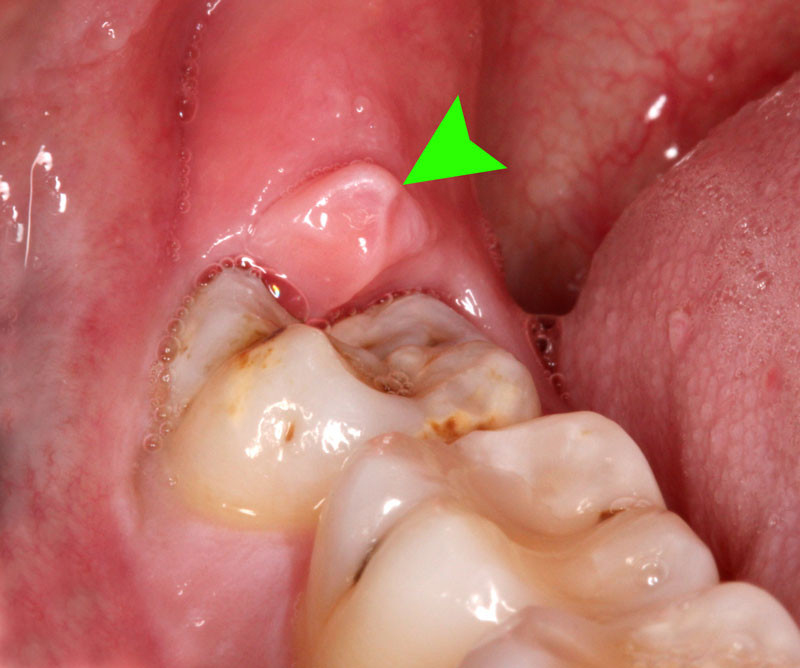

Một số răng khôn có thể mọc ngầm hoàn toàn, tức là chúng không thể trồi lên khỏi nướu mà bị kẹt lại dưới xương hàm hoặc mô mềm. Trường hợp khác phổ biến là răng khôn mọc lệch, đâm xiên vào răng hàm kế bên (răng số 7), hoặc mọc về phía xương hàm hay má. Thậm chí có những trường hợp răng khôn chỉ nhú lên một phần rồi dừng lại, tạo thành một túi nướu che phủ. Những kiểu mọc bất thường này là nguyên nhân chính gây ra các vấn đề sức khỏe răng miệng nghiêm trọng, từ đau nhức cho đến nhiễm trùng và tổn thương cấu trúc răng xung quanh.

Việc thức ăn và vi khuẩn bị tích tụ thường xuyên xung quanh răng khôn đang mọc hoặc mọc lệch rất dễ gây ra viêm nhiễm phần lợi bao quanh nó, một tình trạng gọi là viêm quanh thân răng. Biểu hiện của tình trạng này bao gồm cảm giác đau nhức âm ỉ hoặc dữ dội, sưng tấy đỏ ở vùng nướu, đôi khi kèm theo sốt nhẹ, miệng có mùi hôi khó chịu và thậm chí làm cứng hàm, khiến người bệnh gặp khó khăn trong việc há miệng hoặc ăn nhai.

Viêm lợi quanh răng khôn do tích tụ mảng bám và vi khuẩn.